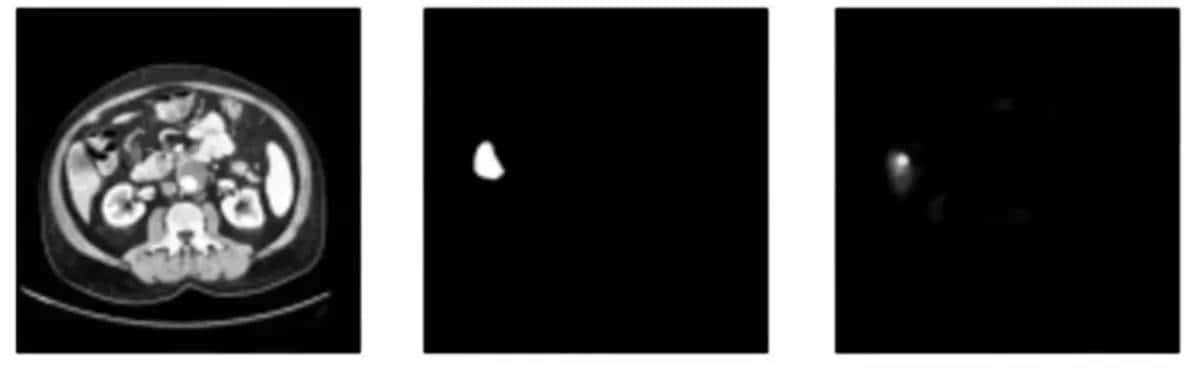

训练效果

为了后面的训练,还要准备好训练用的掩膜DICOM照片,掩模图直接在原图上标记出肿瘤的位置、大小,与原图的每张照片一一对应,由标记人员用专用工具逐张标记后生成:

前面说过CT照片实则是立体模型的切片,实际肿瘤不必定占满整个立体模型,因此为了加快训练速度,可以将没有拍到肿瘤的照片剔除,只留下拍到有肿瘤的照片以及对应的人工标记好的掩模图。

筛好照片后,将原照片和掩模图按顺序对应分别导出为JPG或PNG等可以被用于训练的格式。